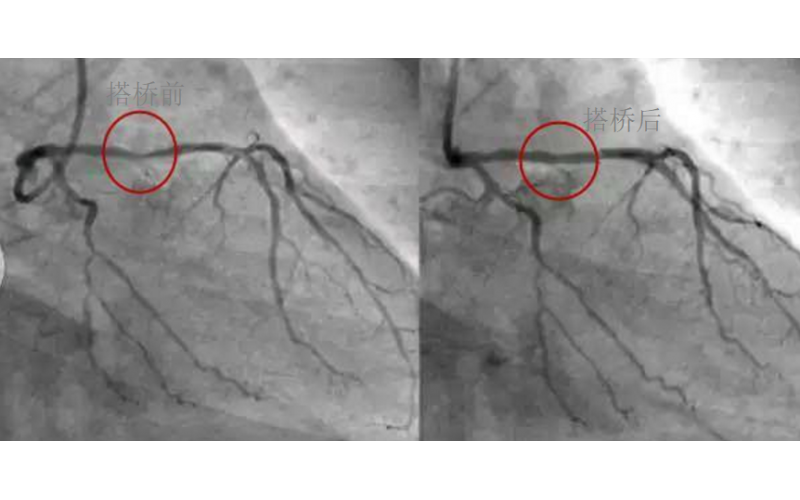

深圳市球盟会官网登录入口厂对心脏支架的关注,国产化的道路有多长?